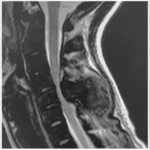

Hidatidosis vertebral

Pedro L. Bazán, Juan Manuel Velasco, Lucas León, Micaela Cinalli

Tratamiento de la hidatidosis vertebral y factores que influyen en la recidiva local. Revisión sistemática

Micaela Cinalli, Gustavo Zubieta Orihuela, Carlos A. Álvarez Martini, Abril Arrue, Pedro L. Bazán